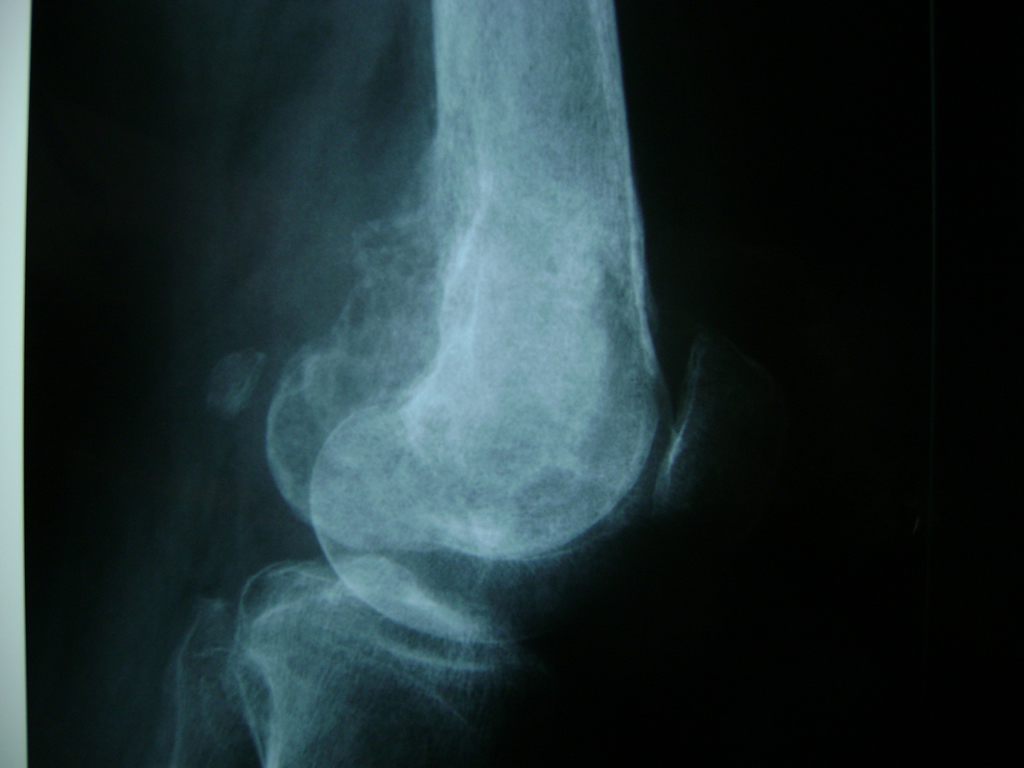

Cirugías de Calcaneo - Rodilla

La artroscopia de rodilla es un cirugía en el cual la estructura interna de la articulación es examinada ya sea para realizar un diagnostico o para realizar un tratamiento, este procedimiento se realiza utilizando un instrumento parecido a un pequeño tubo llamado artroscopio.